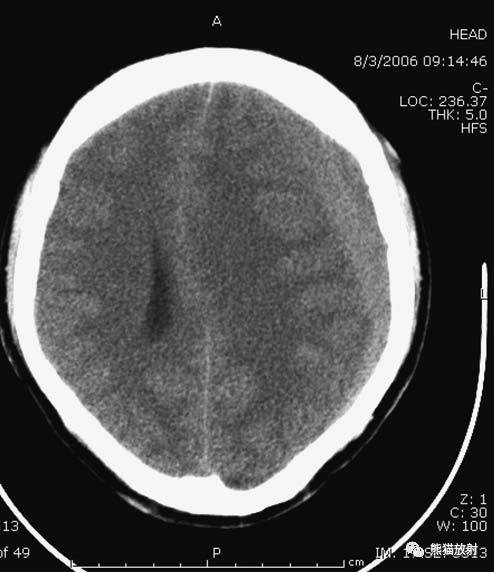

6、脑梗死

缺血性脑卒中。早期:脑水肿,灰白质分界模糊,脑沟消失;中期:病变区域密度减低;晚期:脑实质体积缩小。

左侧大脑中动脉供血区脑梗死(亚急性期):低密度,轻度水肿。

缺血性脑卒中发作2-4天时,占位效应最明显。